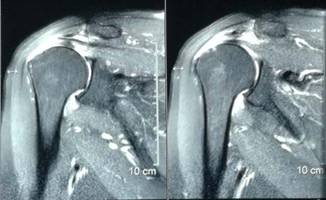

另外,微创成为我院关节科的一大亮点,膝关节周围截骨术,单髁置换术都是微创手术,患者创伤小,恢复快。我院关节科采用直接前路微创髋关节置换术,切口小,只有8-10cm,顺肌间隙进入,不切断任何肌肉,出血少,无痛,关节脱位率低,术后康复快。关节镜下微创肩袖撕裂修补,冻结肩松解,肩关节撞击症肩峰下减压术,膝关节交叉韧带损伤修补等手术,避免大切口、大创伤、恢复快。

全膝关节表面置换术治疗重度骨性关节炎、全髋关节置换术治疗晚期股骨头坏死、先天性髋关节发育不良、股骨颈骨折。微创钻孔减压、腓骨移植、髋关节外科脱位大转子截骨技术治疗股骨头坏死。直接前路微创髋关节置换术。膝关节周围截骨术、单髁置换术阶梯治疗膝关节骨性关节炎。人工反置式肩关节置换术治疗巨大肩袖损伤;关节镜下微创肩袖撕裂修补术,肩峰下减压术及肩关节脱位的手术。髋膝关节置换术后翻修术。

关节镜下肩袖损伤修复术治疗肩袖损伤

优点:损伤小、恢复快。

反肩置换术治疗重度肩袖损伤、肱骨头坏死等

优点:关节外科领先技术。